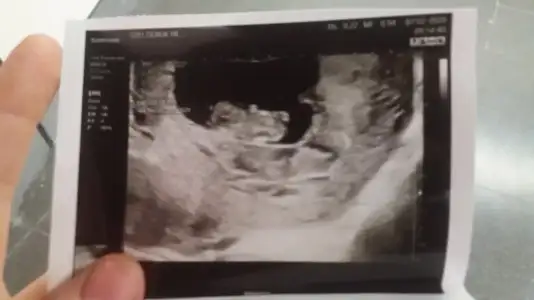

Merhaba. 11+2’deki USG icin cinsiyet tahmininizi alabilir miyim? İlk goruntu karindan usg, digeri vajinal usg. Tesekkur ederim.

C43296EA-BDBC-40E0-84B3-21D0955395DF.webp 5A258968-852F-4229-9D07-ABD4784CBBD3.webp